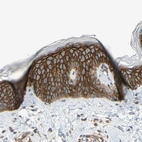

Immunohistochemical staining of human rectum shows strong cytoplasmic positivity in glandular cells.